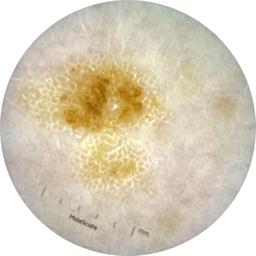

ISIC_9785574

2003 x 2003

Field Value

acquisition_day 148

age_approx 45

anatom_site_1 Head and neck

anatom_site_general head/neck

concomitant_biopsy False

diagnosis_1 Benign

diagnosis_confirm_type single image expert consensus

family_hx_mm True

image_manipulation instrument only

image_type dermoscopic

lesion_id IL_0236417

patient_id IP_8456088

personal_hx_mm True

sex female